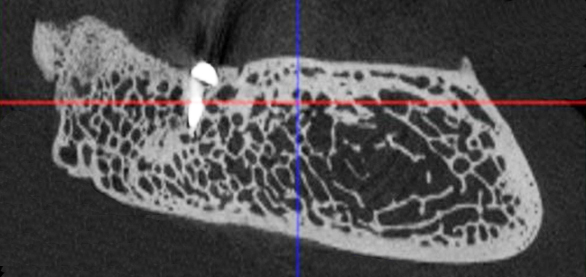

Рис. 1. Поперечный срез микротомографии локтевого отростка овцы

Учитывая выше перечисленные недостатки, поиск новых областей и способов хирургического доступа для создания экспериментальной модели исследования остеопластических материалов является актуальным. Нас заинтересовало использование в качестве экспериментальной живой модели область локтевого отростка передних конечностей овцы. В доступной литературе нами не встречено упоминаний об использовании локтевых отростков овец с целью формирования костных дефектов для оценки регенераторного потенциала остеопластических материалов. Вероятно, это обусловлено боязнью риска травматизма локтевого отростка в ходе формировании дефекта при использовании классического хирургического инструментария – сверл и фрез большого диаметра. Между тем очевиден ряд преимуществ данной области – схожее анатомическое строение и архитектоника с альвеолярной частью челюстей человека. Локтевой отросток имеет наружный кортикальный слой и внутренний, представленный губчатым веществом с костномозговыми пространствами небольшого размера (рис. 1, 2).